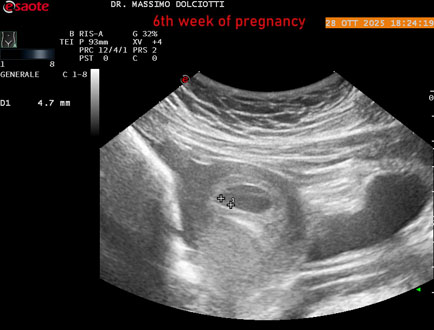

Data inserimento: 29/10/2025

Ecografia del: 28/10/2025

Strumento: Esaote MyLab Eight

Sonda: Convex Multifrequenza 1-8 MHz

Età Paziente: F 35 anni

Motivazione dell'esame: amenorrea.

Commento all'esame: le immagini ed il video documentano in utero il sacco gestazionale, il sacco vitellino e presenza di embrione delle dimensioni di 4,7 mm (CRL), con iniziale attività cardiaca, documentata nel video.

Conclusioni: gravidanza alla 6° settimana di gestazione (pregnancy to the 6th week of gestation).